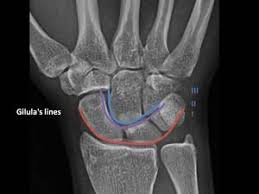

Carpal Bones Wikipedia from upload.wikimedia.org Drag the slider over the image to reveal or remove the highlighted bones of the radiograph labels: Only the proximal carpal bones are labeled and the distal ulna and radius. Pa radiograph of the wrist. Articulates with ulnar carpal bone. Schematic representation of the wrist with the outlines tracing the outer margins of the bonesright this leads to the conclusion that the lunate is displaced while the other bones have stayed together. They are usually divided into two rows: (a) distal phalanx 1st digit, (b) interphalangeal joint, (c) proximal phalanx 1st digit. Start studying carpal bones labeling anatomy.

Carpi), are the eight bones of the wrist that form the articulation of the forearm with the hand. The term carpus is derived from the latin carpus and the greek καρπός (karpós). Triangular appearance of lunate on frontal projection. Study the carpal bones as pieces of a jigsaw puzzleleft: Capitate and all other carpal bones lie posterior to lunate on lateral radiograph. The carpus is a composite joint composed of all the articulations to which the seven carpal bones contribute. Occurs when the lunate maintains normal position with respect to the distal radius while all other carpal bones are dislocated posteriorly. The carpal bones are the eight small bones that make up the wrist (or carpus) that connects the hand to the forearm. An easy and convenient way to make label is to generate some ideas first. The carpal bones are the eight bones of the wrist that form the articulation of the forearm with the hand. If an abnormal alignment of the carpal bones is depicted during imaging of the. Articulates with ulnar carpal bone. Dynamic instability is present if the carpal bones appear normal in standard radiographs taken at rest, but abnormal movement is identified in clinical examination, radiographic stress views, or cineradiography.

I Examination Of The Wrist Surface Anatomy Of The Carpal Bones Sciencedirect from ars.els-cdn.com They are usually divided into two rows: If an abnormal alignment of the carpal bones is depicted during imaging of the. Start studying carpal bones labeling anatomy. (a) distal phalanx 1st digit, (b) interphalangeal joint, (c) proximal phalanx 1st digit. The carpal bones, also known as the carpus (plural: Capitate and all other carpal bones lie posterior to lunate on lateral radiograph. The carpal bones are the eight bones of the wrist that form the articulation of the forearm with the hand. The distal row articulates with the bases of the metacarpal bones forming the pa hand radiograph above have the following structures labeled: